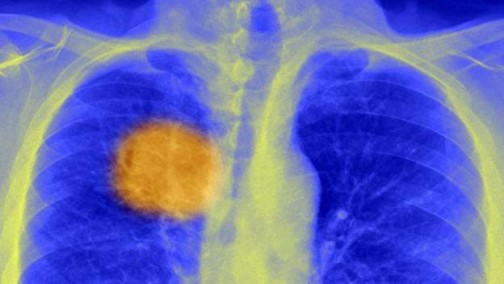

Scientists ‘find cancer’s Achilles heel’

BBC News: Scientists believe they have discovered a way to “steer” the immune system to kill cancers.

They have developed a method, reported in Science journal, for finding unique markings within a tumour – its “Achilles heel” – that the immune system can target.